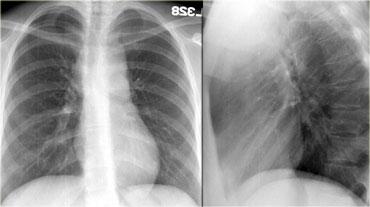

Hãy mô tả các hình ảnh bên trái.

Sau đó tiếp tục.

Trên phim thẳng (PA), có hình ảnh giãn rộng dạng múi của trung thất trên.

Trên phim nghiêng ngực, khoang sáng sau xương ức bị xóa mờ.

Đây là trường hợp bệnh nhân mắc u lympho.

Bên trái là hình ảnh FDG-PET của cùng bệnh nhân.

Có nhiều khối hạch bạch huyết ở trung thất trước, trung thất giữa và thậm chí trung thất sau, lan lên vùng cổ.